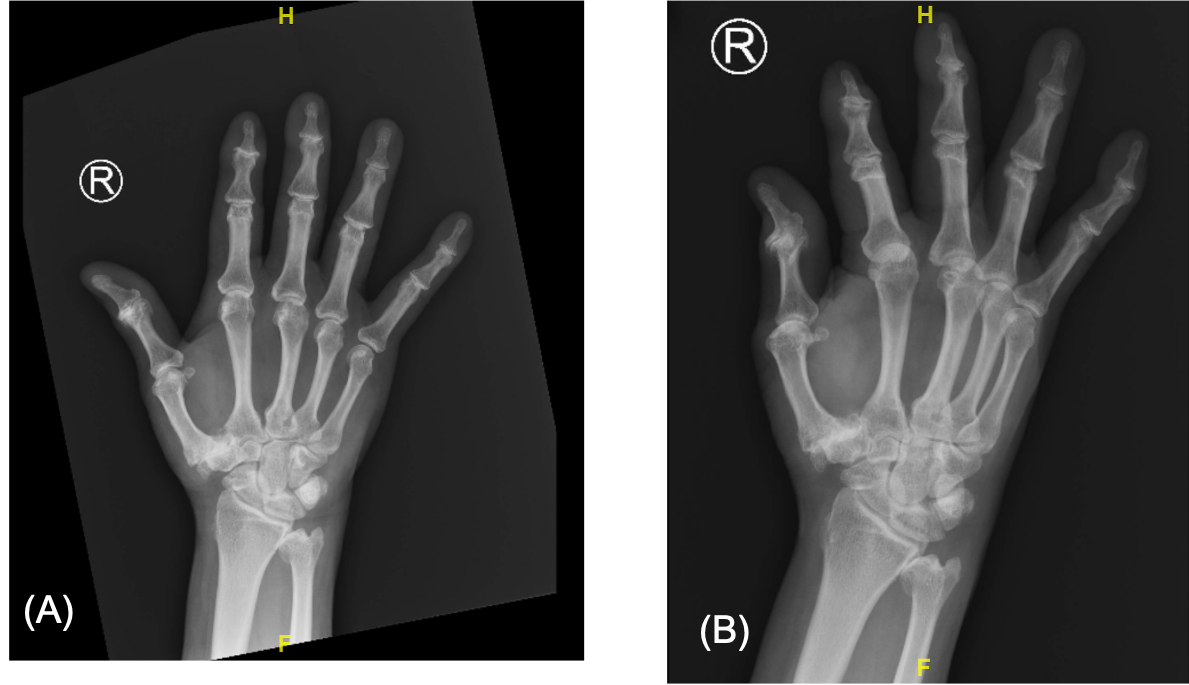

Radiographs of the right hand and wrist demonstrated negative ulnar variance, with severe osteoarthritic changes of the DRUJ evidenced by marginal osteophytes, joint-space narrowing, and subchondral sclerosis on either side of the joint (Figures 1 and 2). Mild deformity of the distal ulnar also raised the possibility of previously unrecalled trauma.

Figure 2. Posteroanterior and oblique radiographs of the right hand demonstrating severe osteoarthritic changes of the DRUJ, with marginal osteophytes, joint-space narrowing, and subchondral sclerosis on either side of the joint. There were also severe osteoarthritic changes visualized in the carpometacarpal and interphalangeal joints of the thumb.